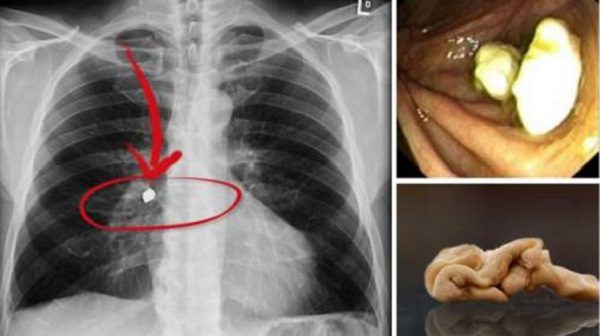

不过如果口香糖吞下去,没有顺利向下经由肠子、肛门排出,在胃里不断混合食物搅动,口香糖就会和食物形成一团球状物,变成胃结石,会慢慢造成肠阻塞,出现肚子痛、呕吐现象,所以为了健康,还是不要把口香糖吞进肚子比较好。